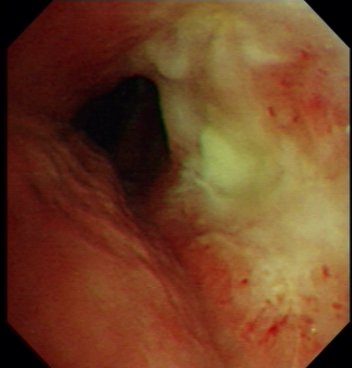

Figure 7: A cancer case was misclassified as a normal case (a), a normal case was misclassified as a cancer case (b), a TB case was misclassified as a cancer case(c)

Figure.  7 shows examples of misclassified cases. Figure. 7a indicates a cancer case that has pale mucosa and yellow secretion and was mis-classified as a normal case by CAD, while Figure. 7b indicates a normal case that has smooth red mucosa and was mis-classified as a cancer case by CAD. Figure. 7c. indicates a TB case that has a round nodule with smooth mucosa and was mis-classified as a cancer case by CAD. Mucosa color, secretions and smoothness are important features for cancer discrimination. In cancer cases, the tumor mucosa is pale, rigid and has dirty secretion. The mis-classification in Figure. 7 might be due to a small dataset for training. Larger training set would extract more minor mucosa features to avoid such mis-classification.